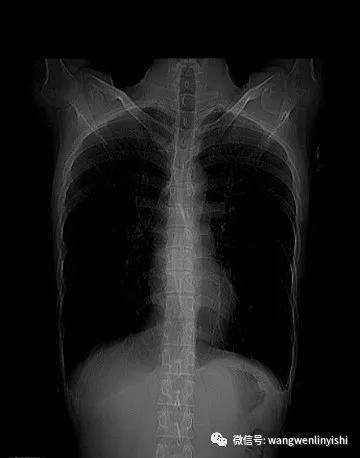

最近我们接诊了一位重度扁平胸患者。患者男性,20岁,前胸壁极度扁平,正常胸廓弧度消失。侧面看前后胸壁间距离明显缩短,且上下一致,脊柱生理弯曲消失,合并直背综合征。X线检查正位片提示胸廓较宽,肋骨水平;侧位片提示胸壁前后径缩短,胸骨与脊柱近似平行,生理弯曲消失,心脏和肺明显受压。

(X线正位片)